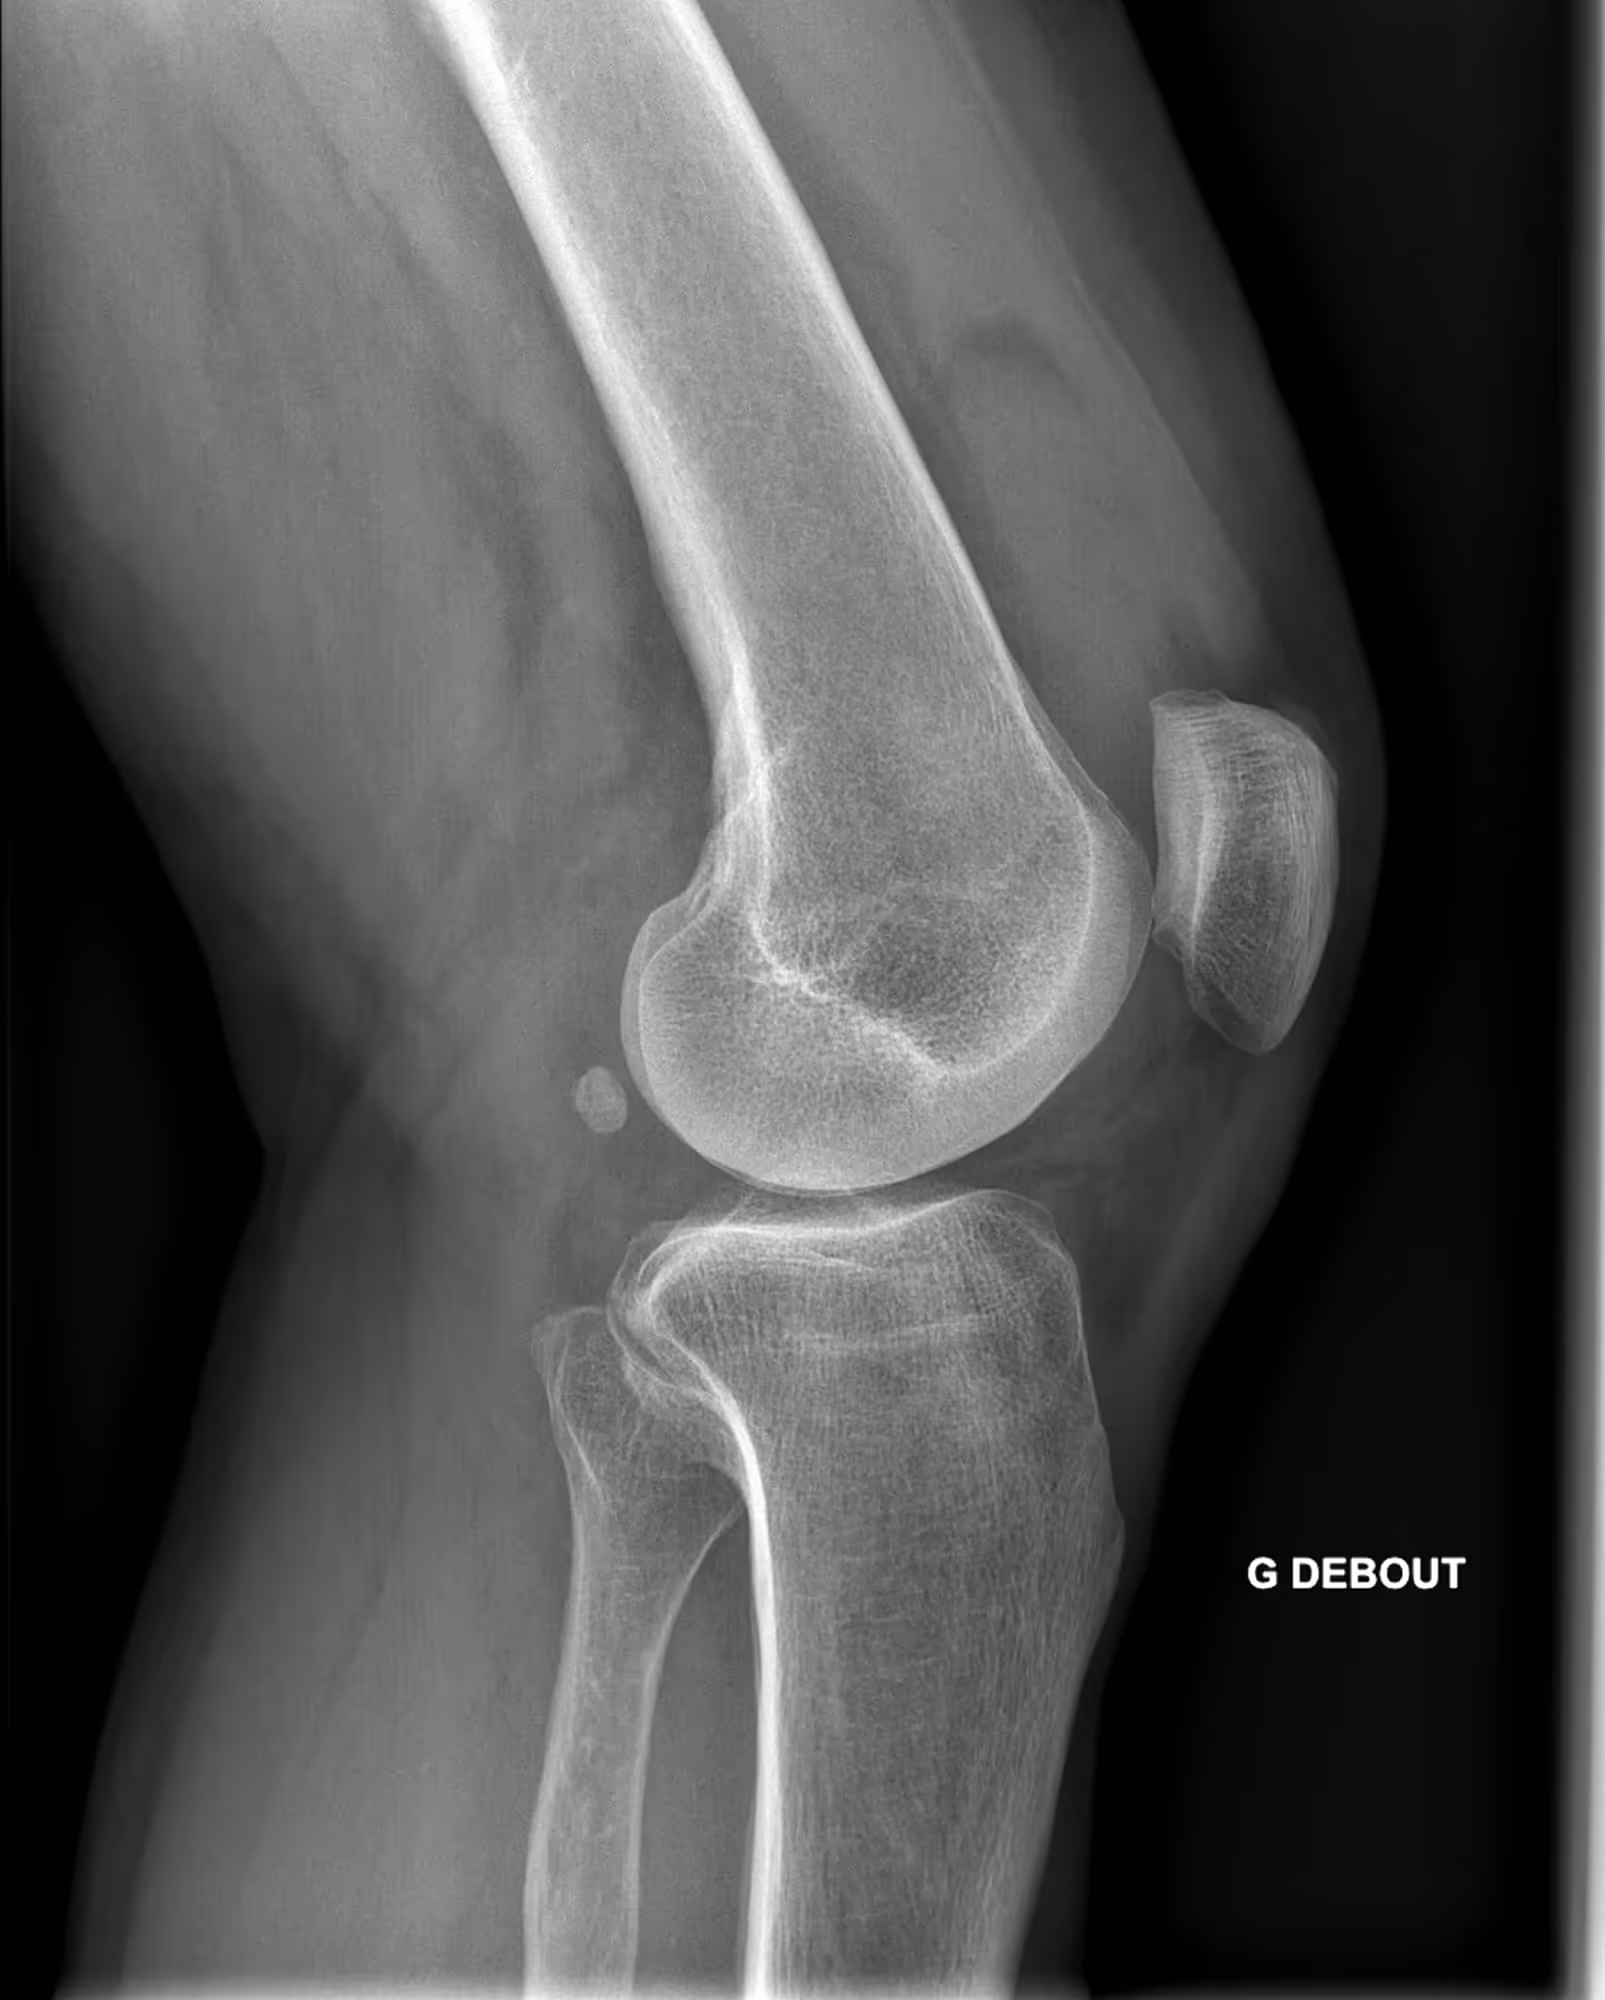

A 63-year-old male with lingering pain after a trail run.

BoneView detected a fracture of the lateral tibial plateau and associated effusion. The fracture has a high risk of displacement.